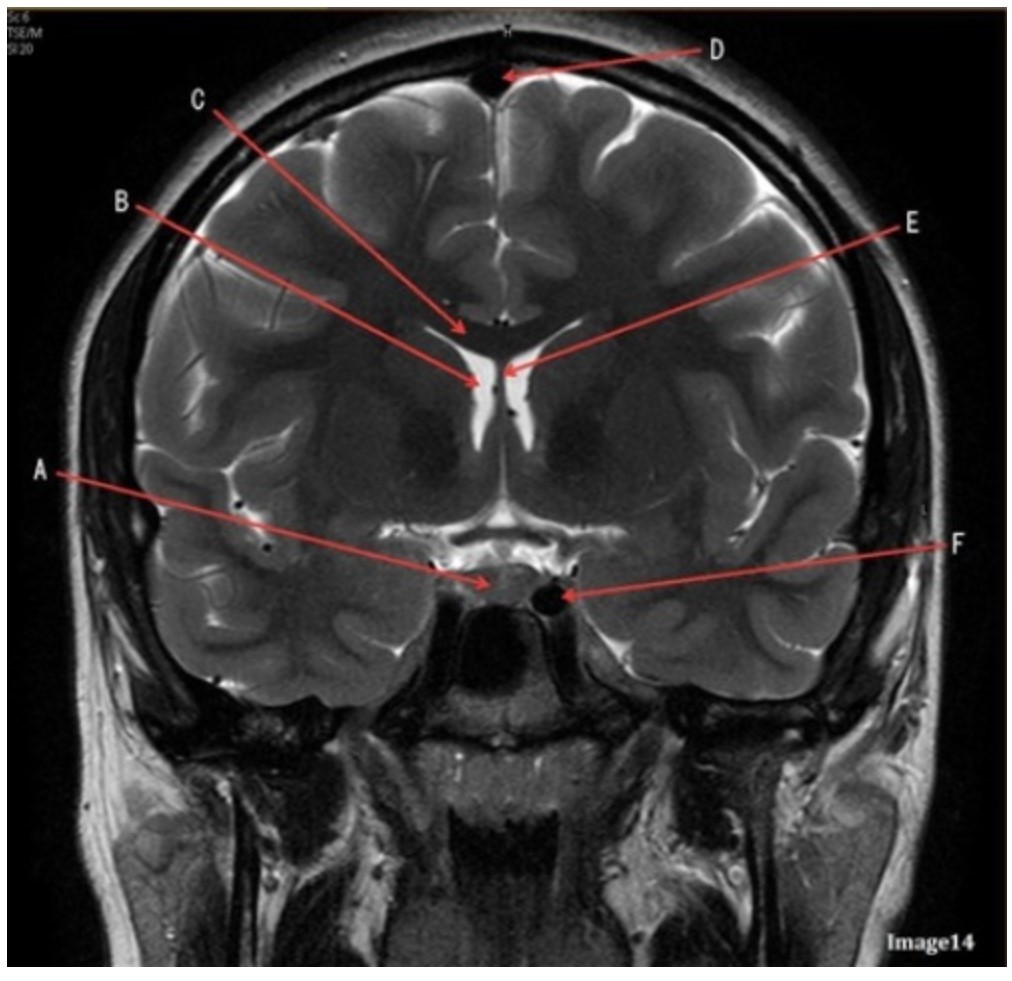

Letter F in Image 14 is pointing to:

A. Third ventricle

B. Pituitary gland

C. Hypothalamus

D. Internal carotid artery

Letter C in Image 14 is pointing to:

A. Corpus callosum

B. Third ventricle

C. Lateral ventricle

D. Pituitary gland

E. Fornix

Letter D in Image 14 is pointing to:

A. Tentorium

B. Sphenoid sinus

C. Frontal sinus

D. Sagittal sinus

E. Fornix

Letter B in Image 14 is pointing to:

A. Corpus callosum

B. Third ventricle

C. Lateral ventricle

D. Pituitary gland

E. Fornix

Letter E in Image 14 is pointing to:

A. Corpus callosum

B. Third ventricle

C. Lateral ventricle

D. Internal carotid artery

E. Fornix

Letter A in Image 14 is pointing to:

A. Corpus callosum

B. Third ventricle

C. Lateral ventricle

D. Pituitary gland

E. Fornix

Letter A in Image 14 is pointing to:

A. Corpus callosum

B. Third ventricle

C. Lateral ventricle

D. Pituitary gland

E. Fornix